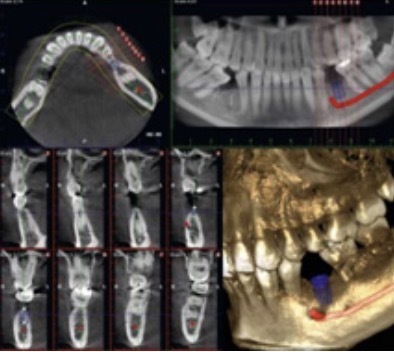

全国の歯科医院の3%にしか入っていないと言われる歯科用コンビームCT。ピュアスマイル原田歯科クリニックでは 歯周病や根の治療、インプラントの診断で活躍しています。

従来のレントゲン写真は、立体的な顎を 平面上に写し出すため、診断に限界がありました。コンビームCTなら立体的に顎を写すことができるため、従来は見ることのできなかった 歯の外側や内側、神経や血管との位置関係を見ることができるようになりました。

ピュアスマイル原田歯科クリニックでは歯周病や根の治療、インプラントの診断で活躍しています。従来のレントゲン写真は、立体的な顎を平面上に写し出すため、診断に限界がありました。

コンビームCTなら立体的に顎を写すことができるため、従来は見ることのできなかった歯の外側や内側、神経や血管との位置関係を見ることができるようになりました。

歯科用CTは、被爆量は2(前歯または奥歯限定で写す場合)、または6(顎全体を写す場合)、医療費9800円ですが、標準型(デンタル)やパノラマ写真では絶対に写らない(従ってきちんと診断できない)歯の裏側、顎の病気、根の治療をしてもなかなか治らない病変、歯周病で骨がどのように溶けているかを3D(立体的)画像で撮影することができ、正しい診断 → 適切な治療方針 → その結果、治療期間の短縮、医療費の節約 が可能です。